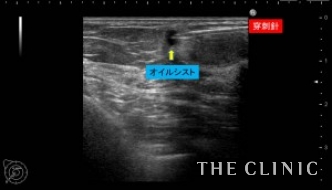

この方は、10年前に脂肪注入を受けられていて、近年の乳がん検診にてしこりを指摘されたとのこと。指摘後は何もせず放置していたが、昨年ぐらいから自分でもしこりを感じるようになったため、当院を受診されました。

しこりの大きさは3mmから7mmと非常に小さなしこりでしたが、ご本人が治療を希望されたためエコー下に穿刺吸引しました。右のしこりの1つは乳腺内の腫瘤でしたが濃縮のう胞でした。

吸引した脂肪です。両側合わせて12個のオイルシストを穿刺吸引しました。